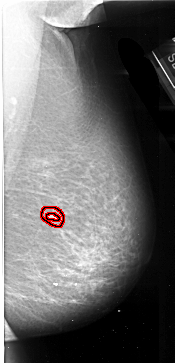

A_1009_1.LEFT_MLO

LEFT_MLO LINES 6016 PIXELS_PER_LINE 3526 BITS_PER_PIXEL 16 RESOLUTION 42 NON_OVERLAY

FILE: A_1009_1.RIGHT_MLO.OVERLAY

TOTAL_ABNORMALITIES 1

ABNORMALITY 1

LESION_TYPE MASS SHAPE IRREGULAR MARGINS SPICULATED

ASSESSMENT 4

SUBTLETY 1

PATHOLOGY MALIGNANT

TOTAL_OUTLINES 2

BOUNDARY

CORE